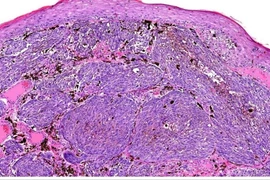

| Ảnh minh họa. |